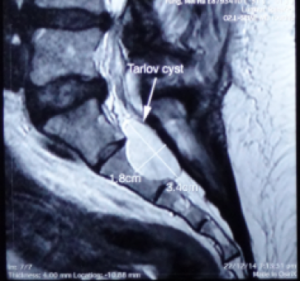

骶管襄腫